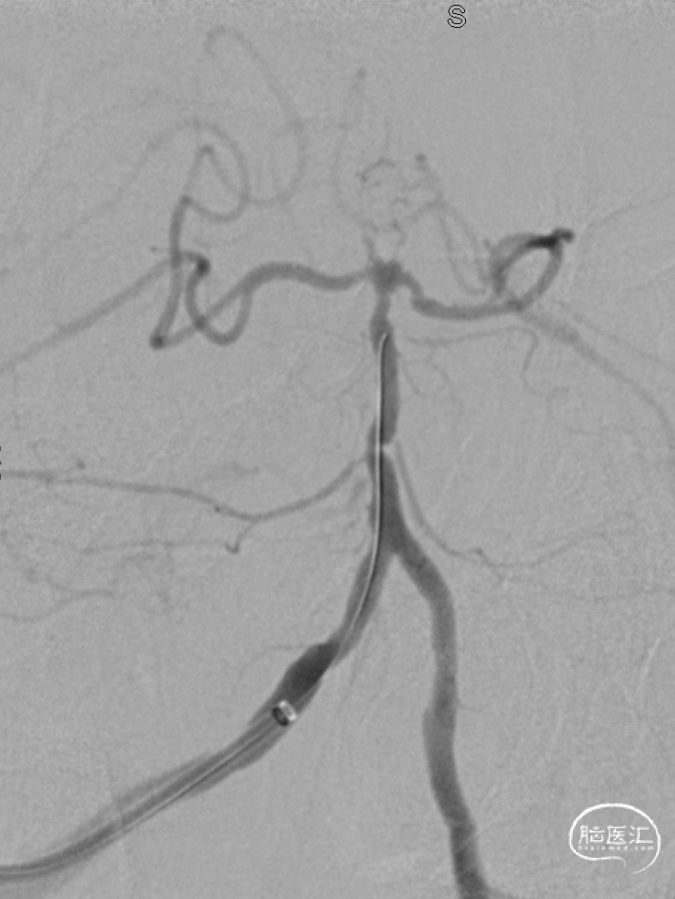

经桡入路造影

术前DSA:双侧后交通动脉开放。

R-CCA

L-CCA

R-VA

L-SUB-VA

6F 90cm 长鞘+5F 115cm 通桥银蛇®颅内支持导管建立通路。